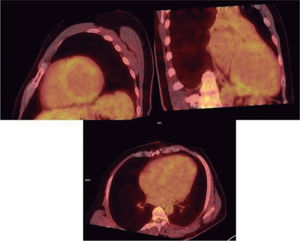

La miocardiopatía dilatada (MCD) es una entidad clínica caracterizada por dilatación ventricular izquierda o biventricular y disfunción sistólica, en ausencia de enfermedades de carga o isquémicas suficientes para justificarla. Su etiología es heterogénea e incluye factores genéticos, infecciosos, tóxicos, metabólicos y autoinmunes. Clínicamente, pueden observarse desde formas asintomáticas hasta situaciones de insuficiencia cardíaca avanzada, arritmias o muerte súbita. El diagnóstico se basa en la integración de hallazgos clínicos, de imagen y biomarcadores, destacando el papel de la resonancia magnética cardíaca y las pruebas genéticas en la evaluación etiológica y pronóstica. El tratamiento incluye terapia médica con inhibidores del sistema renina-angiotensina-aldosterona (SRAA), bloqueadores beta-adrenérgicos, antagonistas del receptor de mineralocorticoides (ARM) e inhibidores del cotransportador de sodio-glucosa tipo 2 (iSGLT2), además de dispositivos como el desfibrilador automático implantable (DAI) o la terapia de resincronización cardíaca (TRC) en pacientes seleccionados. En situaciones avanzadas refractarias a tratamientos anteriores, el trasplante cardíaco o los dispositivos de asistencia ventricular representan opciones a considerar. La identificación precoz de factores de riesgo permite una mejor estratificación pronóstica y optimización terapéutica en esta compleja patología.

Dilated cardiomyopathy (DCM) is a clinical entity characterized by left ventricular or biventricular dilatation and systolic dysfunction in the absence of an abnormal loading condition or ischemic disease to justify it. Its etiology is heterogeneous and includes genetic, infectious, toxic, metabolic, and autoimmune factors. Clinically, it can range from asymptomatic forms to advanced heart failure, arrhythmias, or sudden death. The diagnosis is based on the set of clinical, imaging, and biomarker findings, with the role of cardiac magnetic resonance imaging and genetic testing of note in the etiological and prognostic evaluation. Treatment includes medical therapy with renin-angiotensin-aldosterone system (RAAS) inhibitors, beta-adrenergic blockers, mineralcorticoid receptor antagonists (MRAs), and sodium-glucose cotransporter type 2 inhibitors (SGLT2i), in addition to devices such as an implantable cardioverter defibrillator (ICD) or cardiac resynchronization therapy (CRT) in selected patients. In advanced situations refractory to previous treatments, heart transplantation or ventricular assist devices are options to be considered. Early identification of risk factors allows for a better prognostic stratification and treatment optimization in this complex disease.